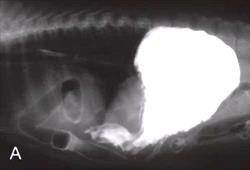

Figure 1.

Lateral and ventrodorsal radiographs from a dog with a peritoneopericardial diaphragmatic hernia following barium administration. Notice the markedly enlarged cardiac silhouette with variable radiographic densities and how the barium administration outlines the bowel loops which traverse the diaphragm and are contained within the pericardial sac. Click on image to see a larger view.

Thoracic radiographs are extremely helpful in establishing a definitive diagnosis of PPDH. Radiographic abnormalities may include: overlap of the caudal cardiac silhouette and cranial diaphragm, variable radiographic densities within the cardiac silhouette, gas-filled bowel loops crossing the diaphragm, and sternal malformations. Oral administration of barium may help outline bowel loops present within the pericardial sac (Figure 1). Ultrasonography can readily identify the presence of abdominal viscera within the pericardial sac and help establish a definitive diagnosis.